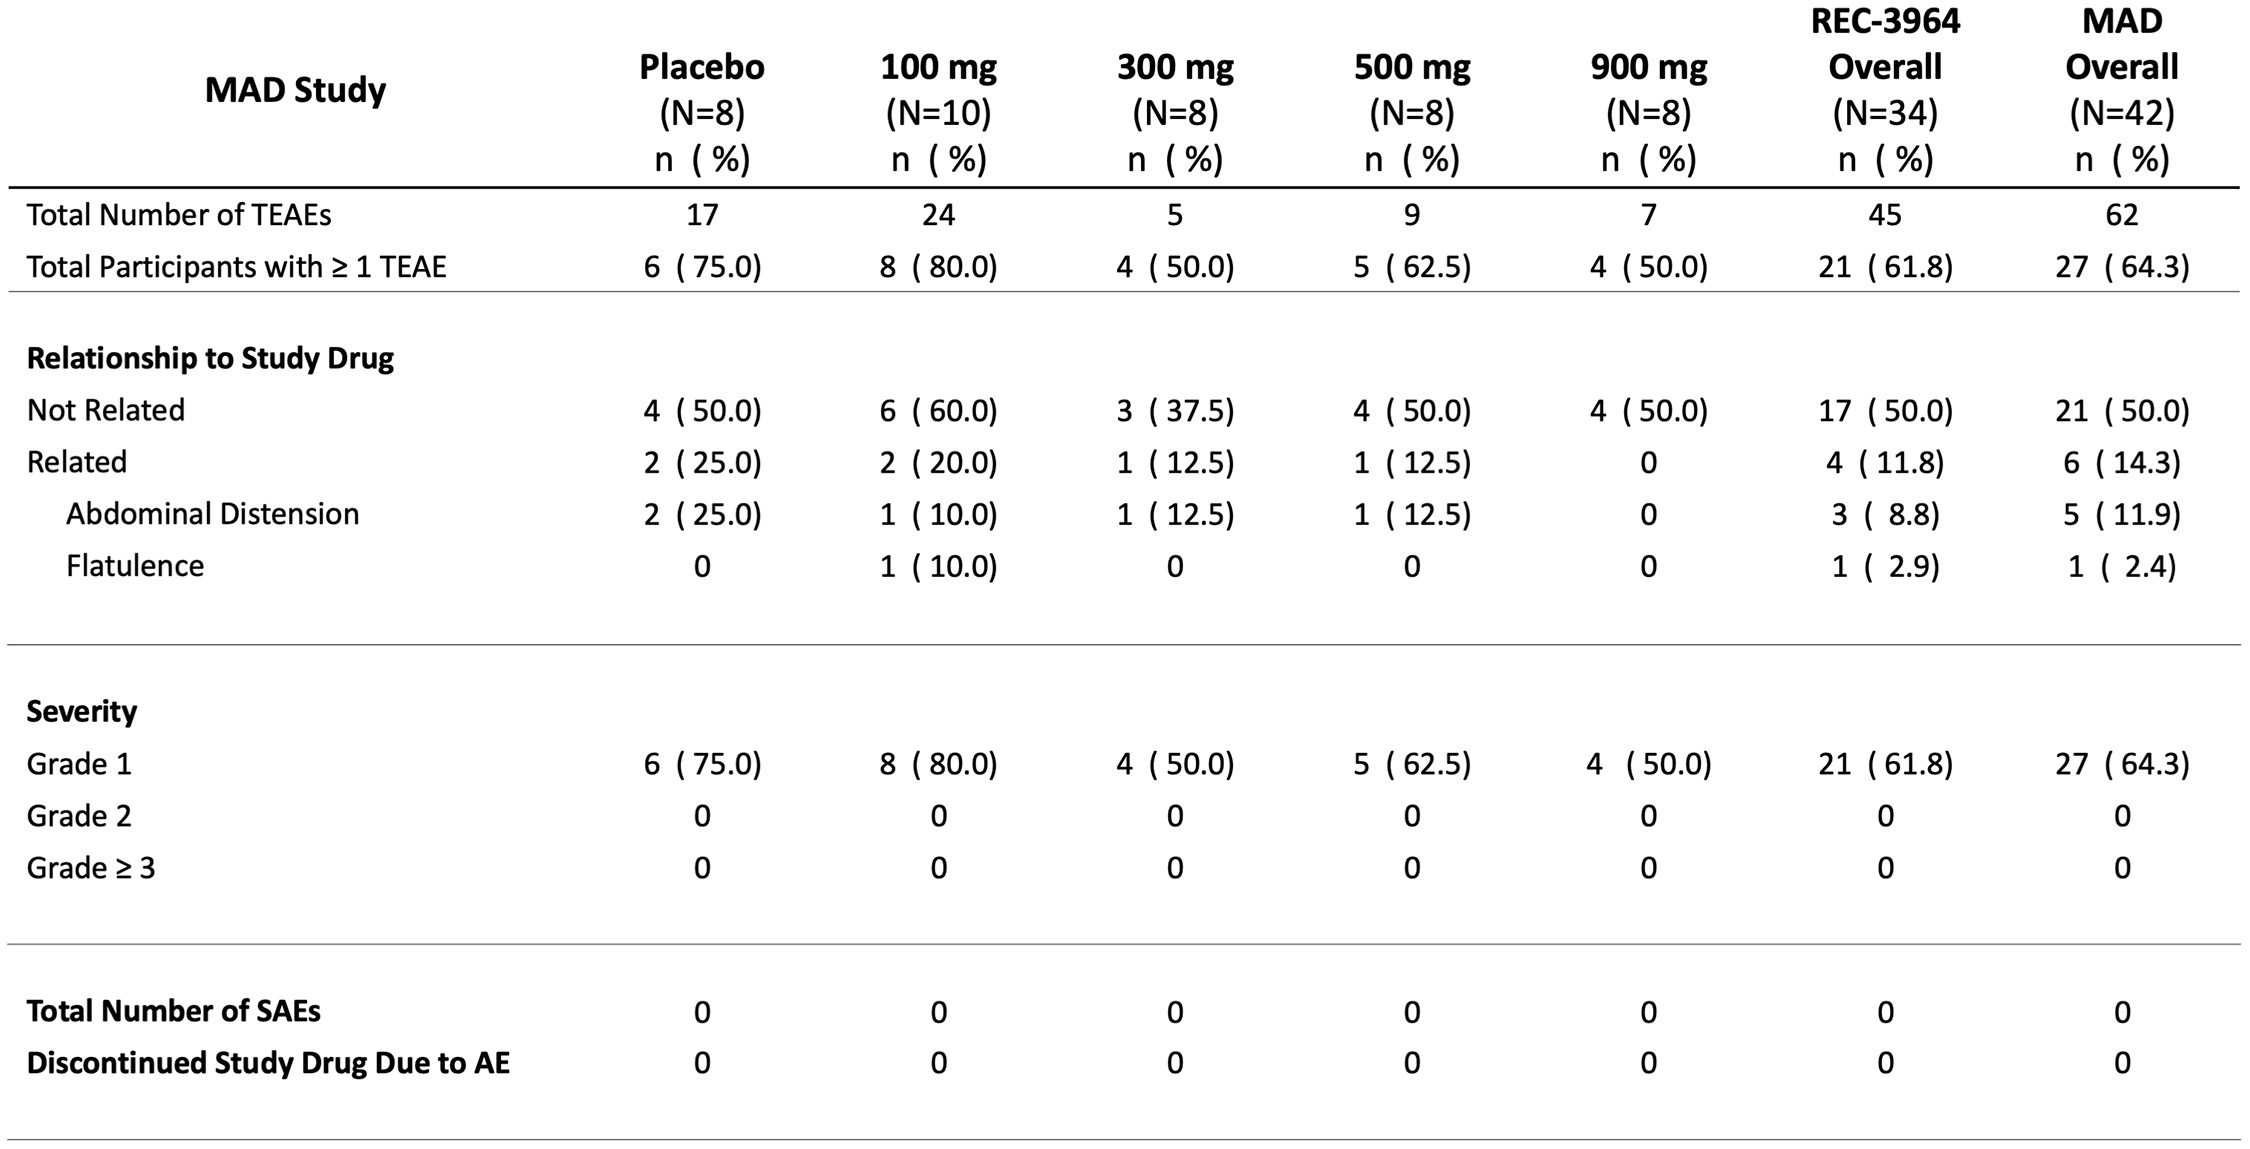

•Completed a Phase 1 study for REC-3964 in healthy volunteers for the potential treatment of Clostridioides difficile (C. difficile) infection with a favorable safety and tolerability profile